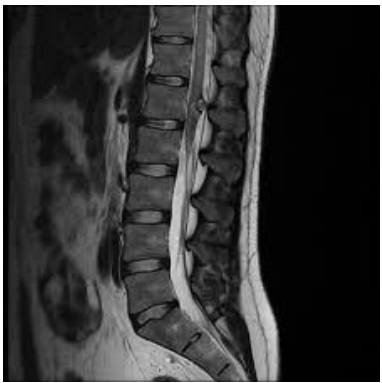

• MRI Brain and Spine: Imaging revealed an expansile intramedullary lesion in the distal thoracic spinal cord and conus medullaris with minimal enhancement, consistent with transverse myelitis.

Fig 3: spine highlighting a lesion in the conus medullaris